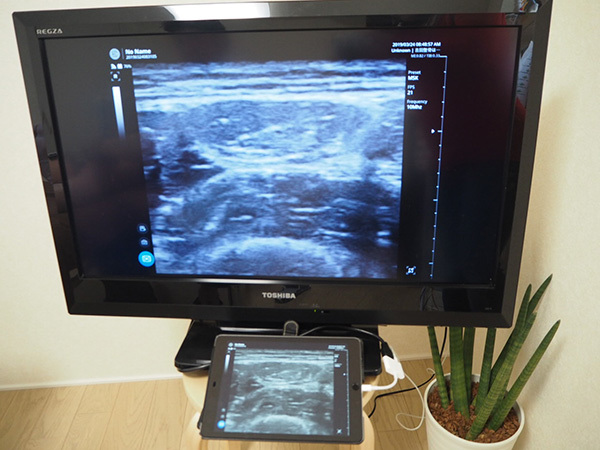

当院では、治療を行う前に十分な評価・ヒアリングを行います。その中で、エコー検査を実施します。スポーツ外傷・傷害は、レントゲンでは確認しにくいことが多いのが現状です。エコー検査を病院ではなく、こういった治療院で行うことは珍しいですが、リアルタイムにケガをしている部位の詳細を確認し、経過をしっかりと画像としても確認していくことを重要視しています。

リアルタイムに身体内の状態を確認することが可能な超音波画像診断装置(エコー)を設置しています。

なので、スポーツで起こりやすいケガで、かつレントゲンでは確認しにくい損傷の確認が可能です。